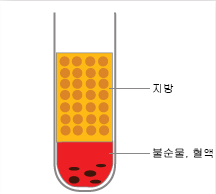

분리된 순수한 지방

자가지방이식은 복부, 허벅지 등에서 필요한 지방을 흡입 채취하여 정제한 후 순수 지방을 미세하게 소량씩 팔자 주름선을

자가지방이식은 복부, 허벅지 등에서 필요한 지방을 흡입 채취하여 정제한 후 순수 지방을 미세하게 소량씩 팔자 주름선을

중심으로 주입하여 생착률을 높여줍니다. 자연스럽게 얼굴 전체에 볼륨감 있는 라인으로 만들어주고, 반영구적인 효과가

있습니다.